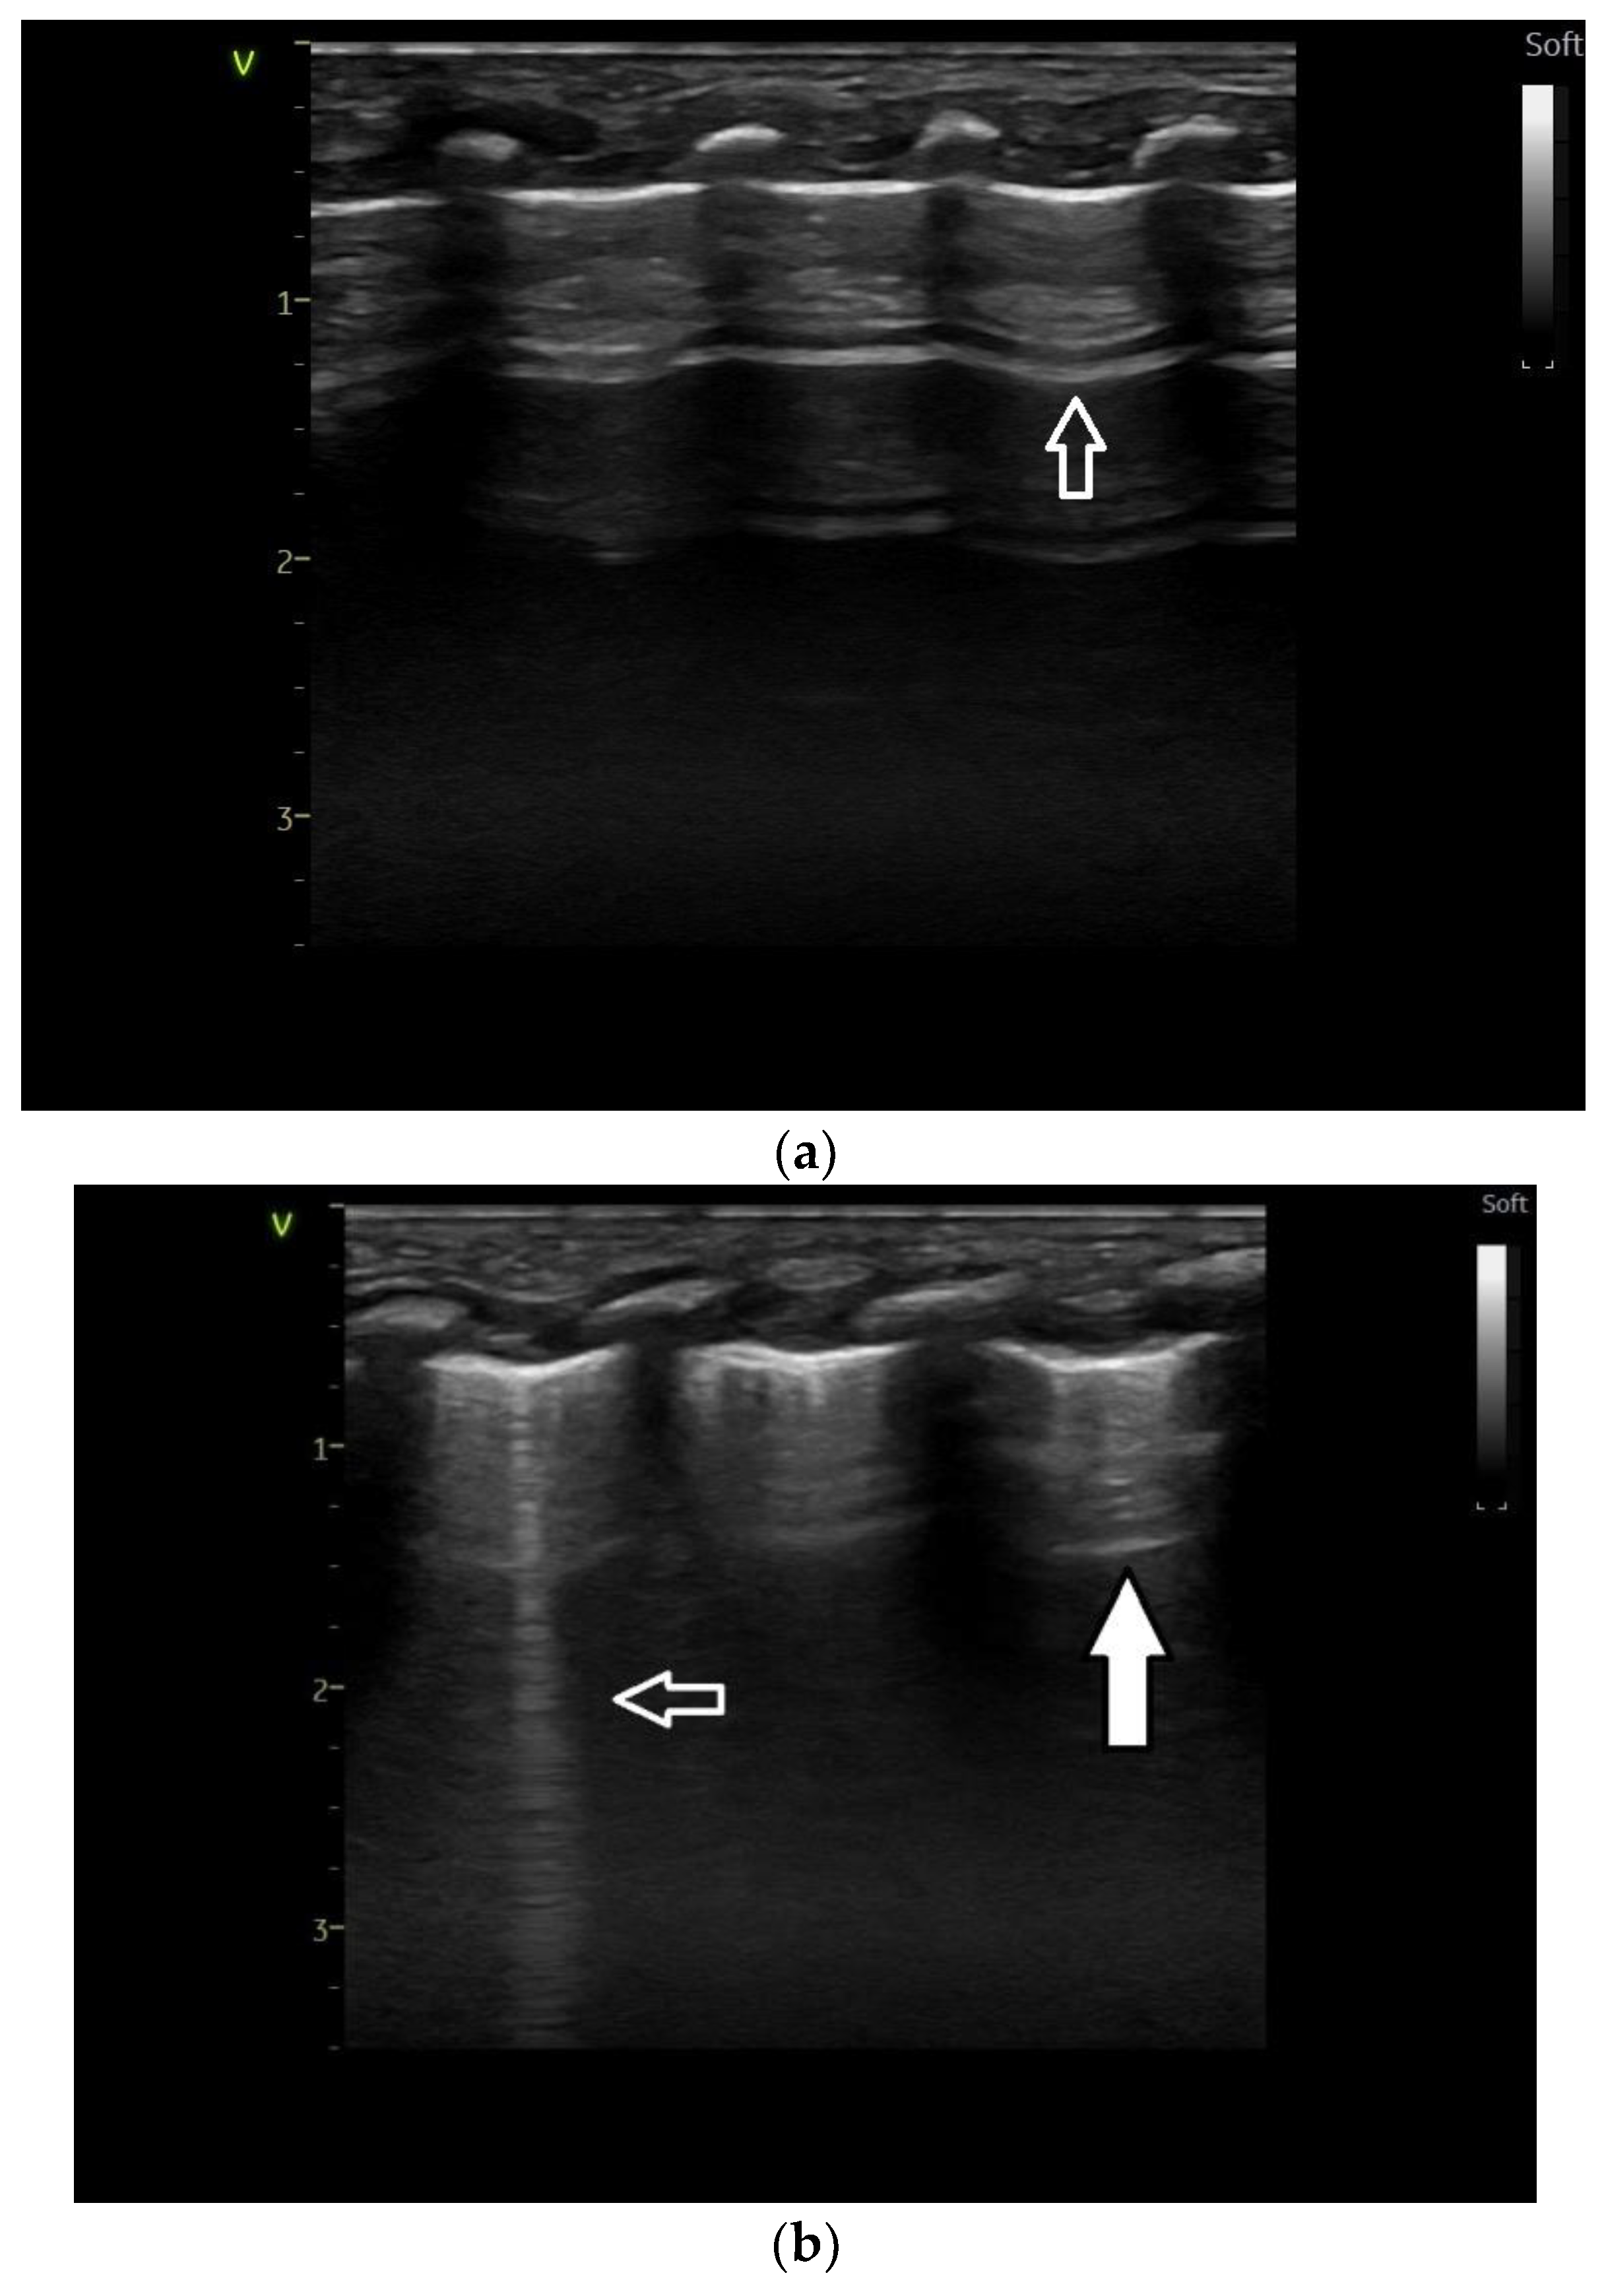

Lung ultrasound